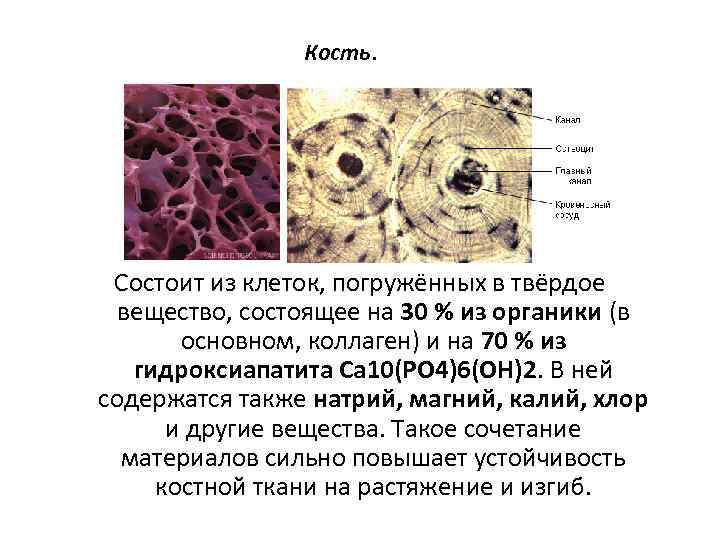

Структура грубоволокнистой костной ткани: наглядные примеры